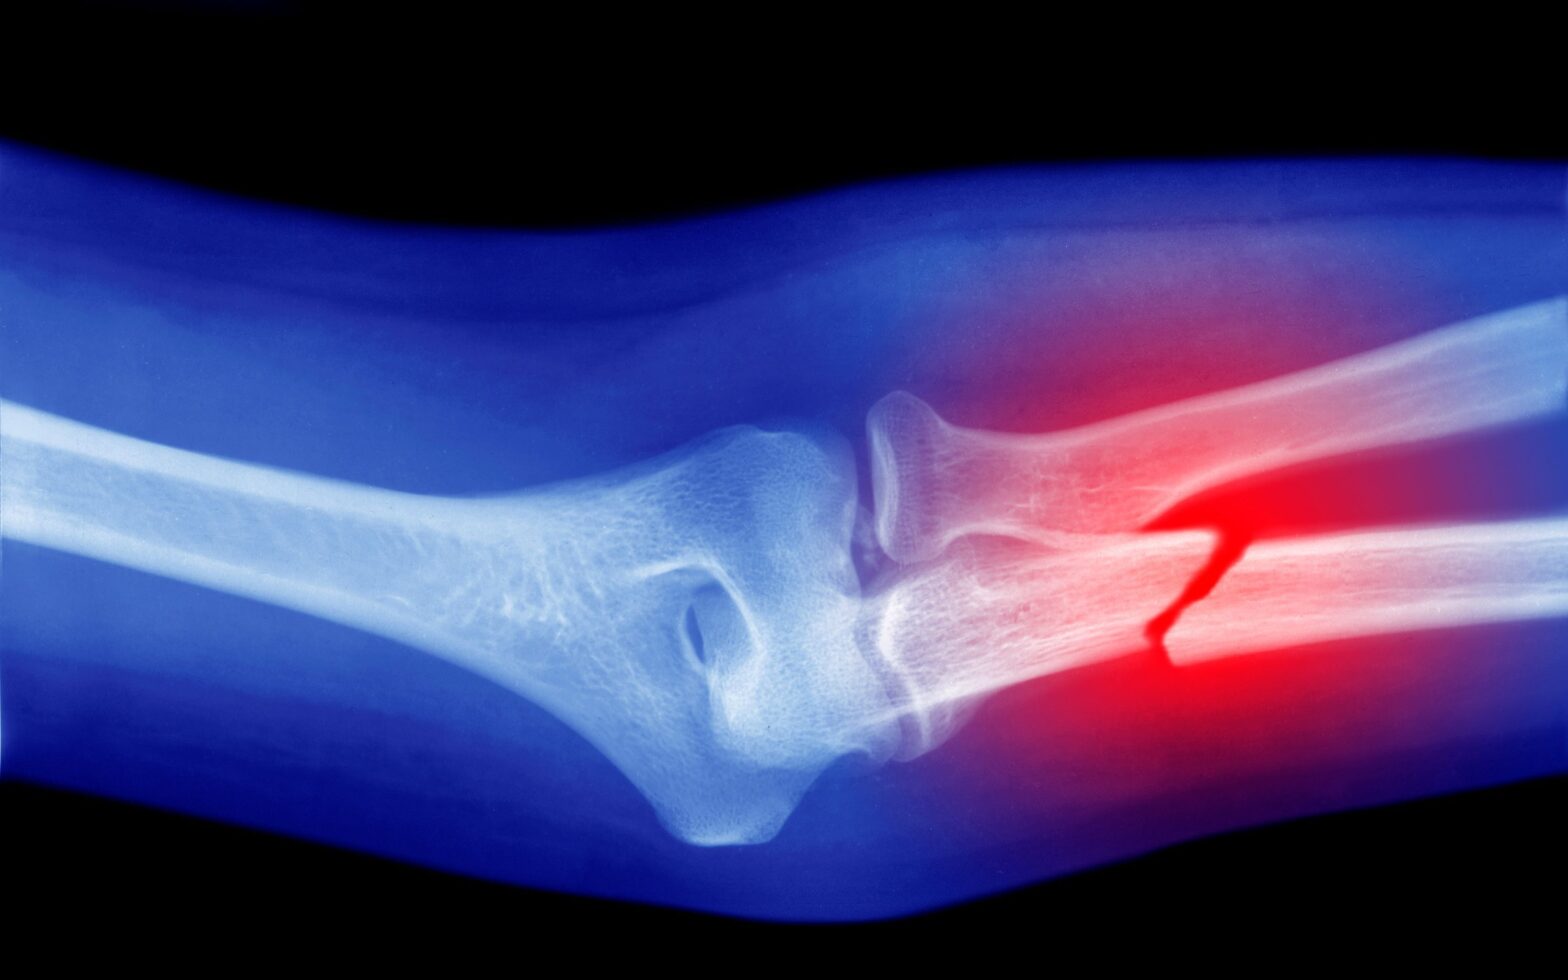

The review of more than 60 scientific articles showed that microplastics, among other effects, can stimulate the formation of osteoclasts, cells specialized in degrading bone tissue.

Microplastics Could Be Weakening Your Bones, Research Suggests